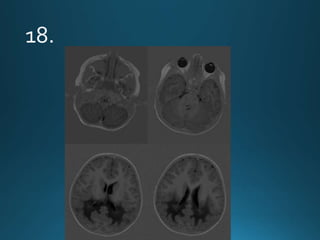

Cerebral Autosomal DominantArteriopathy with Subcortical Infarcts and

Leukoencephalopathy (CADASIL) is characterised by recurrent lacunar and

subcortical white matter ischaemic strokes and vascular dementia in young and

middle age patients without known vascular risk factors

autosomal dominant trait

recurrentTIA and dementia

MRI:

widespread confluent white matter hyperintensities . More circumscribed

hyperintense lesions are also seen in the basal ganglia, thalamus and pons

There is relative sparing of the occipital and orbitofrontal subcortical white matter 2,

subcortical U-fibers and cortex

Cerebral Autosomal DominantArteriopathywith Subcortical Infarcts and Leukoencephalopathy (CADASIL) is characterised by recurrent lacunar and subcortical white matter ischaemic strokes and vascular dementia in young and middle age patients without known vascular risk factors autosomal dominant trait recurrentTIA and dementia MRI: widespread confluent white matter hyperintensities . More circumscribed hyperintense lesions are also seen in the basal ganglia, thalamus and pons There is relative sparing of the occipital and orbitofrontal subcortical white matter 2, subcortical U-fibers and cortex